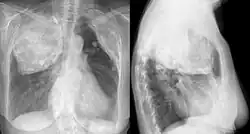

X-ray in an elderly woman after pneumonolysis

Pneumonolysis, sometimes referred to as plombage, is the separation of an adherent lung from the pleura, to permit collapse of the lung. It was formerly used to treat tuberculosis before effective medications were developed.[1]

The technique involved surgically creating a cavity underneath the ribs in the upper part of the chest wall and filling this space with some inert material. A variety of substances were typically used and included air, olive or mineral oil, gauze, paraffin wax, rubber sheeting or bags and Lucite balls. The inserted material would force the upper lobe of the lung to collapse.